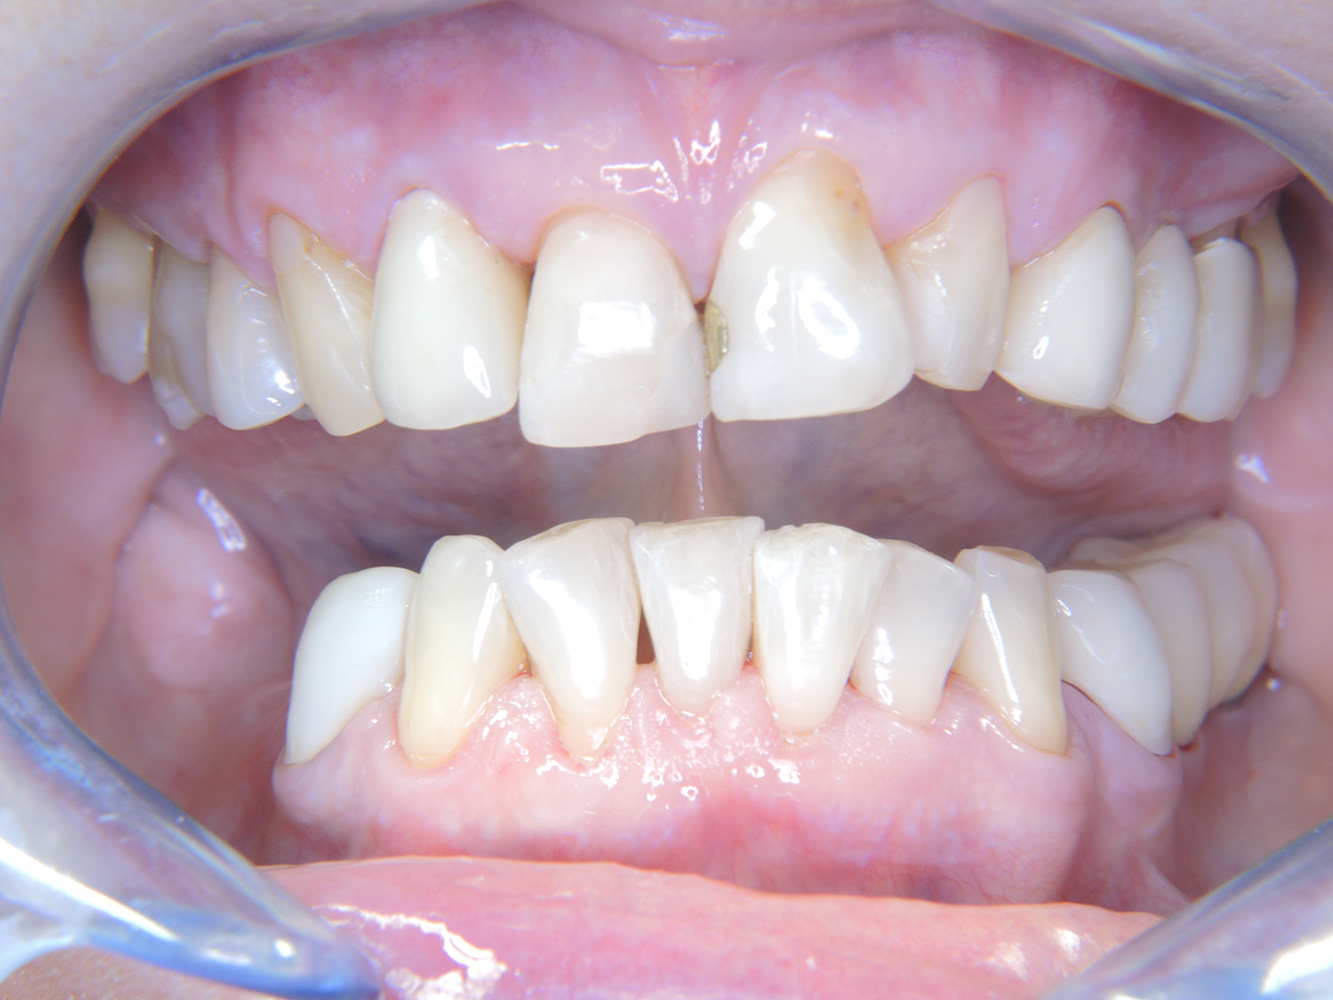

La paciente de 68 años no tiene enfermedades previas relevantes de la salud general ni toma medicación; sus hábitos alimentarios tampoco suponen un riesgo especial. La paciente tiene dos implantes (tercer cuadrante, desde hace cinco años) y una enfermedad previa periodontal (periodontitis en etapa IV, grado B) con pérdida dental. Actualmente las condiciones periodontales son estables, pero la periodontitis aumenta de manera determinante las complicaciones biológicas cuando se realizan implantes y puede ocasionar la pérdida de un implante (21). Para la sesión de profilaxis se hacen cuatro recomendaciones.

Aunque las condiciones sean estables, no debe descuidarse la motivación y la formación de esta paciente. Hay que prestar especial atención a que aprenda a cómo cuidar los implantes correctamente. Aquí en particular, un buen mantenimiento en casa puede jugar un papel importante en la estabilización a largo plazo de la salud oral y del implante.

Al seleccionar el instrumental, se aplica un procedimiento especial en la zona de los implantes. Para conservar la superficie del implante y, al mismo tiempo, limpiarla con eficacia, es crucial seleccionar los instrumentos y los polvos adecuados, como el uso dirigido de aeropulidores con puntas Paro especiales. La elección de los polvos adecuados puede hacerse según las necesidades y los riesgos, por ejemplo, además del grado apropiado de abrasión, pueden tenerse en cuenta los requisitos alimenticios (como que sean sin azúcar o bajos en sal).